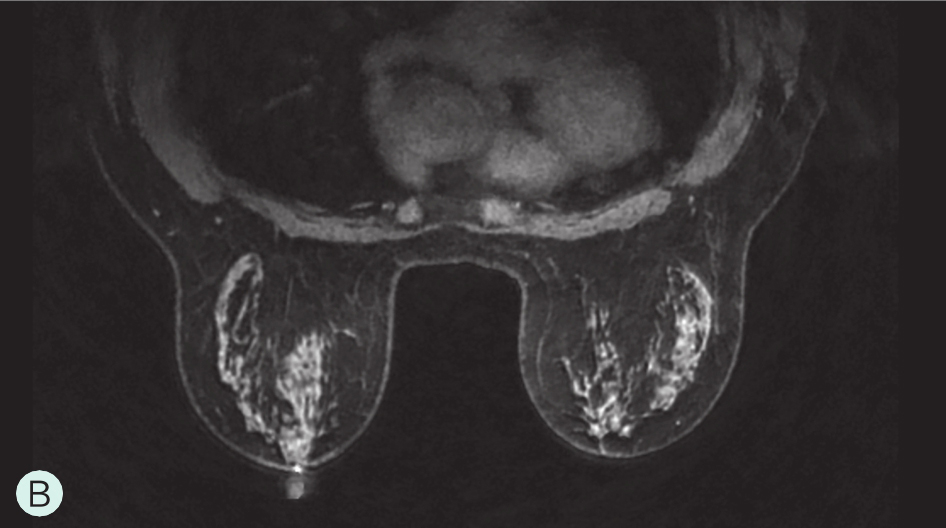

C级:不均匀致密型(可能掩盖小肿块)(图1-3-1C、图1-3-2C、图1-3-3C)。

图1-3-3 乳腺MRI不同乳腺密度

A.脂肪型;B.散在致密型;C.不均匀致密型;D.极度致密型